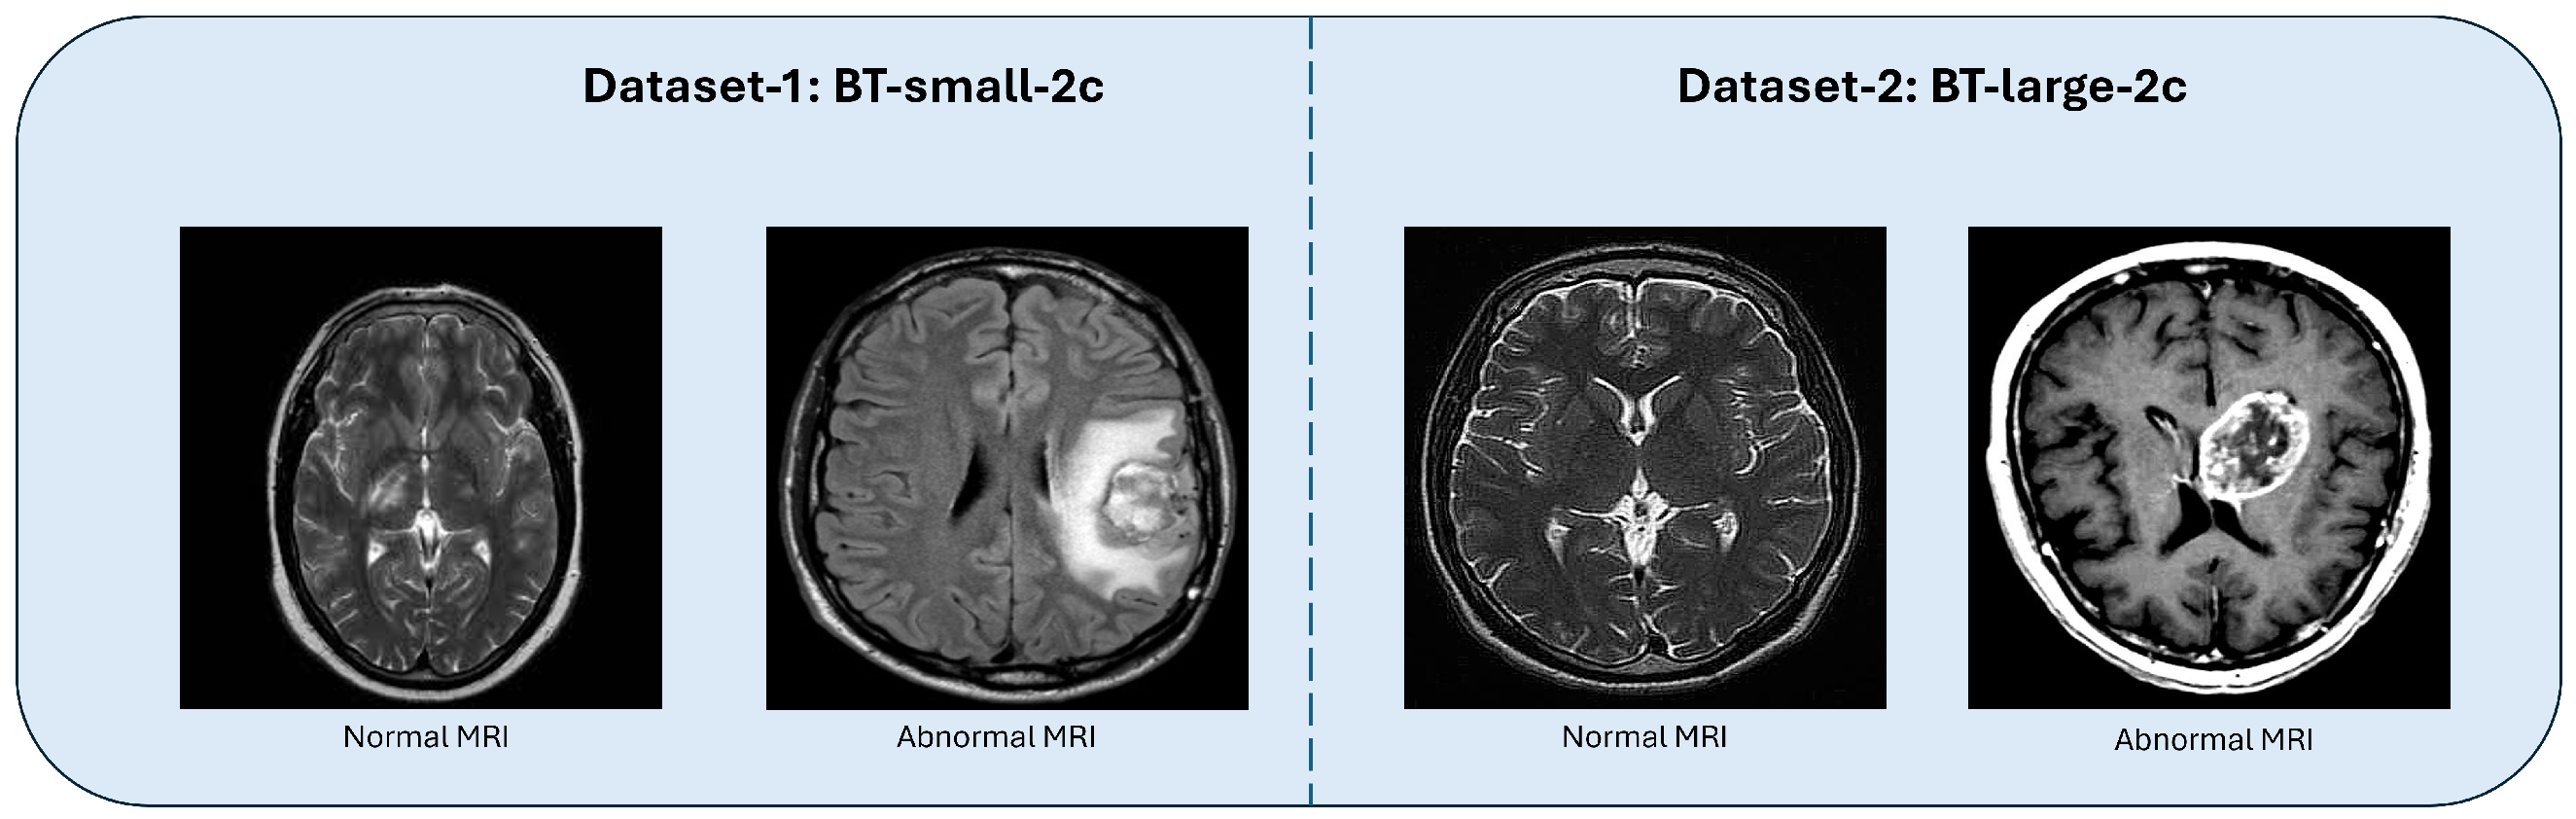

3.3. Datasets

| Types | Number of Classes | Training Set | Test Set |

|---|---|---|---|

| BT-small-2c | 2 | 202 | 51 |

| BT-large-2c | 2 | 2400 | 600 |